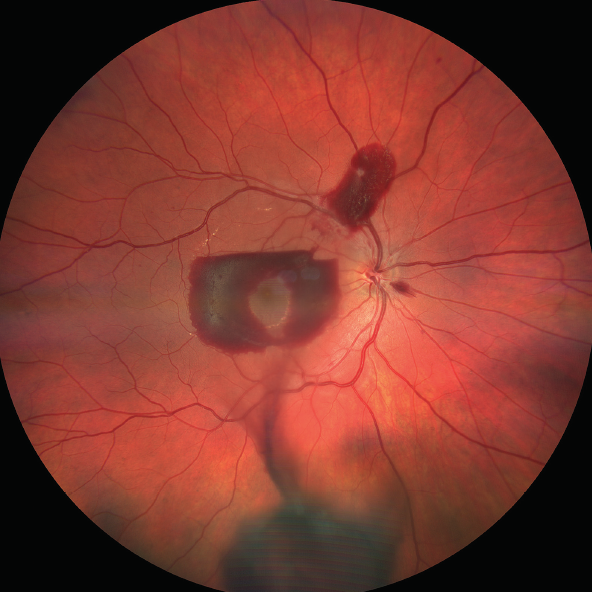

<p>Figure 1. Fundus examination of patient's right eye revealed a donut-shaped subhyaloidal hemorrhage in the macula, a preretinal hemorrhage at the superior arcade, a flame-shaped peripapillary hemorrhage, and an inferior vitreous hemorrhage.</p>

Figure 1. Fundus examination of patient's right eye revealed a donut-shaped subhyaloidal hemorrhage in the macula, a preretinal hemorrhage at the superior arcade, a flame-shaped peripapillary hemorrhage, and an inferior vitreous hemorrhage.

On ocular examination, both anterior segments and the left fundus were normal. Right fundus examination revealed a donut-shaped subhyaloidal hemorrhage in the macula, a preretinal hemorrhage at the superior arcade, a flame-shaped peripapillary hemorrhage, and an inferior vitreous hemorrhage (Figure 1). The diagnosis was thought to be Valsalva retinopathy, despite the patient's assertion.1

Interestingly, the fovea was spared by the subhyaloidal hemorrhage, allowing maintenance of good vision. This can be explained by the typical distribution of vitreomacular adhesion in people in this age group. The posterior vitreous is most adherent at the fovea, the optic disc, and around the arcades, whereas it is less adherent in the mid-macula. The relatively weaker adhesions provided a cleavage plane for the blood to spread in a donut shape, sparing the fovea. The distribution of the subhyaloidal hemorrhage, as well as a stage 1 posterior vitreous detachment,2 were confirmed on OCT (Figure 2).